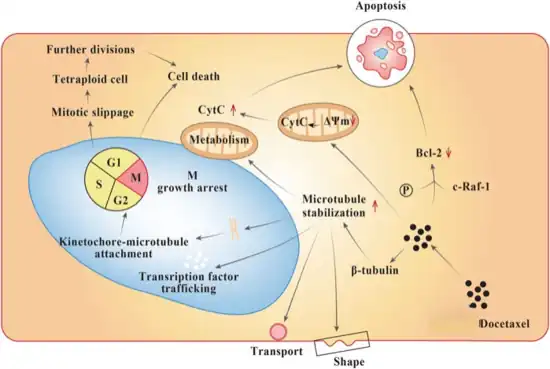

Common side effects include hair loss, low blood cell counts, numbness, shortness of breath, vomiting, and muscle pains.[2] Other severe side effects include allergic reactions and future cancers.[2] Side effects are more common in people with liver problems.[2] Use during pregnancy may harm the baby.[2] Docetaxel is in the taxane family of medications.[4] It works by disrupting the normal function of microtubules and thereby stopping cell division.[2]

As well as inhibiting mitosis, the presence of docetaxel has been found to lead to the phosphorylation of the oncoprotein bcl-2, which leads to apoptosis of cancer cells that had previously blocked the apoptotic inducing mechanism, leading to tumour regression.[9] Enhanced effects of radiation therapy when combined with docetaxel has been observed in mice.[9] Docetaxel has also been found to have greater cellular uptake and is retained longer intracellularly than paclitaxel allowing docetaxel treatment to be effective with a smaller dose, leading to fewer and less severe adverse effects.[17]

Docetaxel binds to microtubules reversibly with high affinity and has a maximum stoichiometry of 1 mole docetaxel per mole tubulin in microtubules.[35] This binding stabilizes microtubules and prevents depolymerisation from calcium ions, decreased temperature and dilution, preferentially at the plus end of the microtubule.[35] Docetaxel has been found to accumulate to higher concentration in ovarian adenocarcinoma cells than kidney carcinoma cells, which may contribute to the more effective treatment of ovarian cancer by docetaxel.[9][35] It has also been found to lead to the phosphorylation of oncoprotein bcl-2, which is apoptosis-blocking in its oncoprotein form.[9]

Modes of action

The cytotoxic activity of docetaxel is exerted by promoting and stabilising microtubule assembly, while preventing physiological microtubule depolymerisation/disassembly in the absence of GTP.[9][17][36] This leads to a significant decrease in free tubulin, needed for microtubule formation and results in inhibition of mitotic cell division between metaphase and anaphase, preventing further cancer cell progeny.[9][14][35]

Because microtubules do not disassemble in the presence of docetaxel, they accumulate inside the cell and cause initiation of apoptosis.[35] Apoptosis is also encouraged by the blocking of apoptosis-blocking bcl-2 oncoprotein.[9] Both in vitro and in vivo analysis show the anti-neoplastic activity of docetaxel to be effective against a wide range of known cancer cells, cooperate with other anti-neoplastic agents activity, and have greater cytotoxicity than paclitaxel, possibly due to its more rapid intracellular uptake.[9]

The main mode of therapeutic action of docetaxel is the suppression of microtubule dynamic assembly and disassembly, rather than microtubule bundling leading to apoptosis, or the blocking of bcl-2.[9][35]

Cellular responses

Docetaxel exhibits cytotoxic activity on breast, colorectal, lung, ovarian, gastric, renal and prostate cancer cells.[9] Docetaxel does not block disassembly of interphase microtubules and so does not prevent entry into the mitotic cycle, but does block mitosis by inhibiting mitotic spindle assembly.[35] Resistance to paclitaxel or anthracycline doxorubicin does not necessarily indicate resistance to docetaxel.[9] Microtubules formed in the presence of docetaxel are of a larger size than those formed in the presence of paclitaxel, which may result in improved cytotoxic efficacy.[17] Abundant formation of microtubules and the prevention of replication caused by docetaxel leads to apoptosis of tumour cells and is the basis of docetaxel use as a cancer treatment.[17] Docetaxel activity is significantly greater in ovarian and breast tumours than for lung tumours.[9]